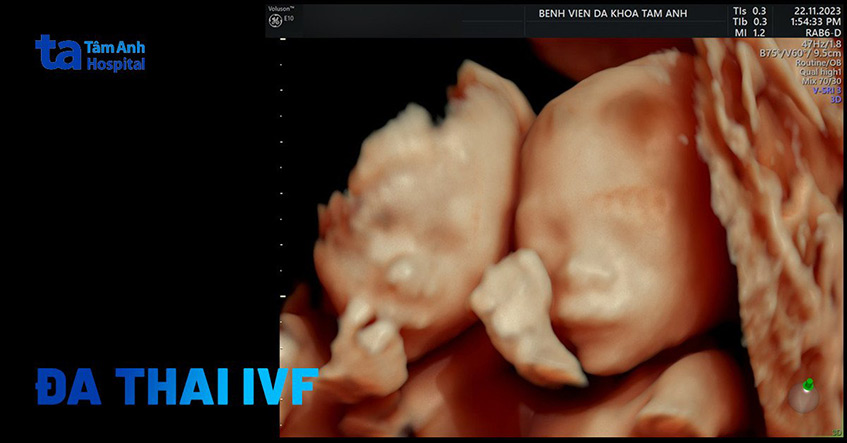

Chuyển nhiều phôi khi thụ tinh ống nghiệm để mang đa thai dễ gặp biến chứng truyền máu song thai, sẩy thai, sinh non, tăng nguy cơ sinh mổ.

Theo PGS Lê Hoàng, tỷ lệ mang đa thai khi thụ tinh ống nghiệm khoảng 20-30%, phần lớn là thai đôi, cao hơn nhiều lần so với thụ thai tự nhiên (chỉ 2%). Bác sĩ thường tư vấn giảm thai, tốt nhất giữ một thai để đảm bảo an toàn cho mẹ và con. Tuy nhiên nhiều gia đình chọn giữ thai đôi bất chấp nguy cơ.